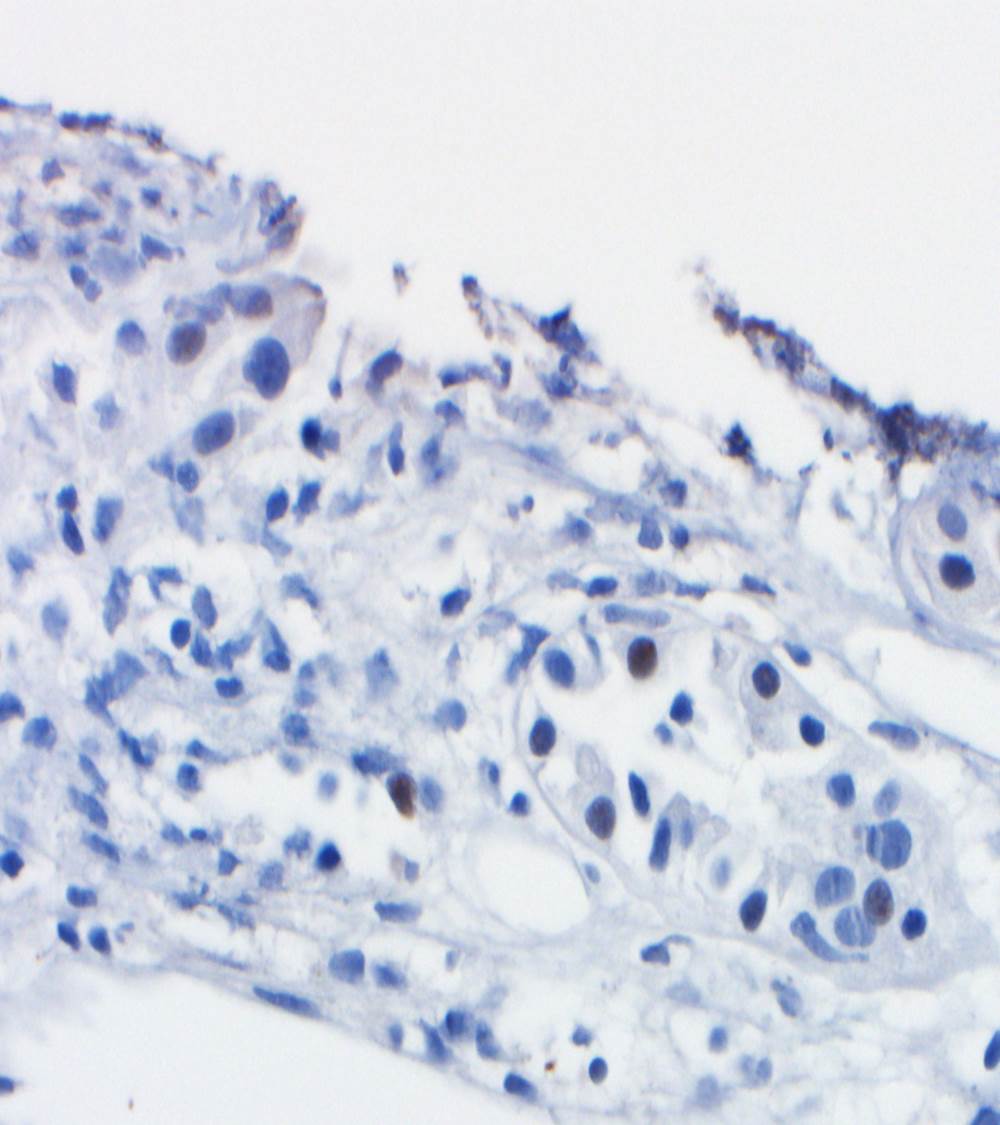

A renal allograft biopsy is essential to differentiate adenoviral nephritis from that of acute rejection or other pathology. Typical light microscopic findings in adenovirus nephropathy include tubular cell necrosis (with tubular basement membrane rupture) associated with severe interstitial inflammation (sometimes with granuloma formation), focal interstitial hemorrhage and viral cytopathic changes including peripheral condensed chromatin, basophilic nuclear inclusions and nuclear enlargement. In some cases such as ours, viral inclusions are not identified, presumably because of the focal nature of viral infection in the kidney. Immunoperoxidase staining can be used to confirm the presence of adenovirus within the nuclei, and to a lesser degree, within the cytoplasm of tubular epithelial cells; although weak, our case showed positive staining. These viral particles are visible under electron microscopy, measuring approximately 75 nm, however they were absent in our patient. Diagnosis in such cases can be clinched by urine examination showing white cell casts and decoy cells, and PCR on the urine testing positive for viral DNA.